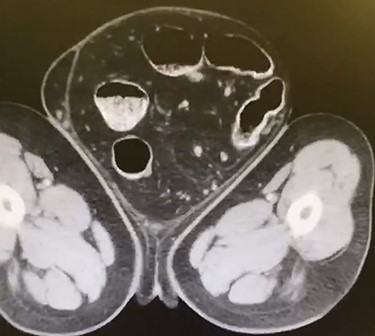

A 66-year-old male with a body mass index (BMI) of 36 presented to the clinic with a GIH of more than 10 years (Fig. 1). It has remained of similar size for the past 5 years and has caused discomfort but without frank pain. A chronically incarcerated umbilical hernia and small right inguinal hernia was also present on exam. Computed tomography (CT) scan showed large amounts of omentum, sigmoid colon, portions of transverse/descending colon and left ureter housed within the 5.7 L inguinoscrotal hernia sac (Figs 2 and 3). Additionally, the left ureter was tortuous and dilated, consequently causing moderate hydronephrosis. The patient was instructed to lose weight and undergo close follow-up in the outpatient setting for preoperative optimization of his preexisting medical conditions, hypertension and hypercholesteremia. He presented 9 months later with a BMI of 31, and an intra-peritoneal catheter was then placed to begin PPP. One liter of carbon dioxide per day was progressively insufflated for a total of 10 days. Concurrently, Deep vein thrombosis prophylaxis was initiated and continued throughout. Following pre-treatment of PPP, midline laparotomy hernia repair (Stoppa technique) was carried out. Manual reduction of incarcerated omentum and sigmoid colon were unsuccessful. Therefore, a counter longitudinal incision was made on the left scrotum, which allowed the sac to decompress for further ease of reduction. Moderate omentectomy was required to allow the delivery of residual omentum and sigmoid colon back into the abdominal cavity. Additionally, left orchiectomy was performed, given the high risk of potential torsion due to the lengthy and redundant pedicle residing in the new vacant hemiscrotum. With the contents fully reduced, a high amount of fascial tension remained. Thus, a bilateral TAR was proceeded in order to further assist in achieving a tension-free closure. Division of the transversus abdominis muscle fibers was attained by hydrodissection. Blunt dissection was then continued throughout the space of Bogros and the space of Retzius, both inferiorly and laterally. This allowed for the fascial layers to meet in the midline in a tension-free manner. Additionally, the small 3-cm right indirect inguinal hernia was identified and was sequentially reduced with an excision of a large cord lipoma. The hernia defects were closed and two 30 × 15 cm pro-grip meshes were placed in a preperitoneal fashion, laying over the myopectineal orifices bilaterally (Stoppa technique). The patient had an additional umbilical defect which was reduced and repaired using an additional piece of 30 × 15 cm pro-grip mesh, oriented cephalocaudally and placed in the retrorectus space for additional ventral support. The scrotal skin was left intact to allow for possible future scrotal reconstruction. The patient was extubated without respiratory complications and discharged home comfortably after an uncomplicated 7-day hospital stay. The patient required left scrotal seroma drainage 2 months postop, which consequently required the excision of the multiloculated cystic collection in the following month. Follow-up ensued once every 2 weeks to ensure optimal wound healing.

Coronal CT displaying sigmoid colon and accompanying abdominal contents traversing into the hernia sac.